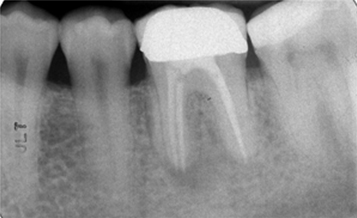

Figure 2: Patient 3. Preoperative periapical radiograph of tooth no. 3.6. Note the radiolucency at the bifurcation and mesial root areas.